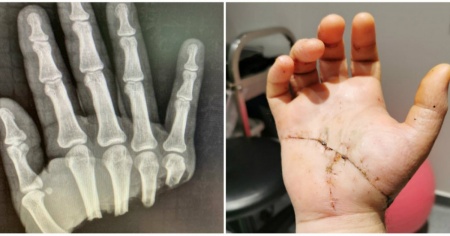

Lawrence Cooper è stato assistito in un ospedale privato, il Mater Private Hospital di Brisbane. Il taglio da sotto il pollice raggiungeva la parte opposta della mano. Il fatto che l’amputazione fosse netta, senza ossa frastagliate, ha reso la situazione meno complicata. Dopo la fase di preparazione, l’operazione di microchirurgia è durata sette ore e mezza. Le ossa, i tendini, i muscoli e infine i vasi sanguigni sono stati riattaccati. Se ci fossero voluti 30 minuti in più, la mano avrebbe iniziato a morire.

Il buon risultato è un miracolo per i medici: il giorno successivo il 23enne muoveva le dita. Dopo l'intervento di fine agosto, la guarigione sarà un processo delicato e lento, ma tutti sperano in un recupero funzionale, fisico e psicologico. Proprio in queste ore il ragazzo ha postato alcune foto su Facebook commentando: «Non è una delle cose migliori che sia mai successa.... Ma si vive e si impara...».